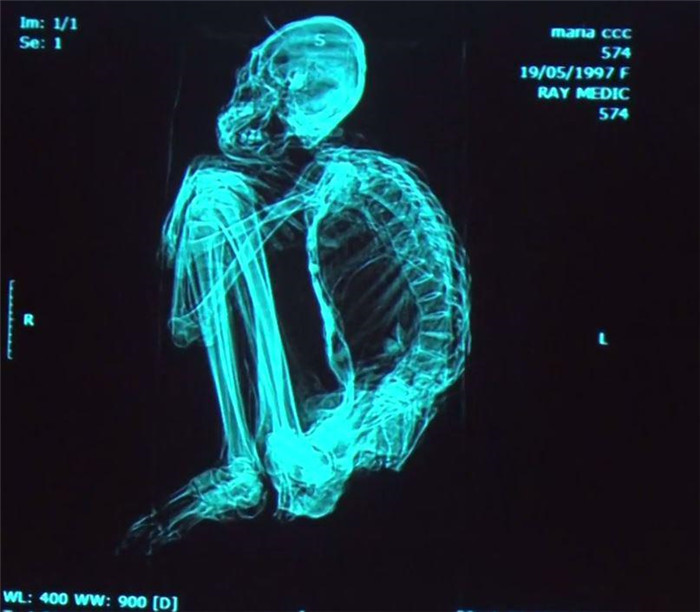

▼頭骨和指頭的X射線显示,干屍是真實的。

▼聖彼得堡大學的教授科羅特科夫(Konstantin Korotkov)博士聲稱,這些3腳趾的乾屍不是畸形,它可能是另一種「類人生物」。